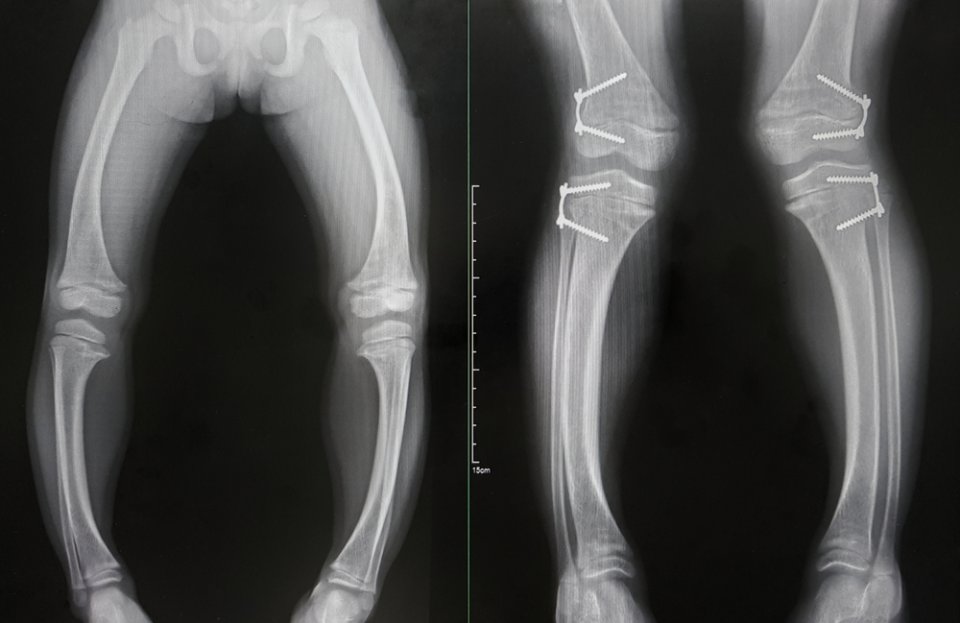

Çocuklarda D vitamini eksikliği şiddetliyse bu durum raşitizme neden olur. Bunun yanı sıra çocuğun büyümesi yavaştır, diş çıkarma dönemi geç başlar ve D vitamini eksikliği olan çocuklar enfeksiyonlara daha yatkındır. Şiddetli vakalarda solunum semptomları ortaya çıkabilir. Zayıf göğüs kasları ve yumuşak göğüs kafesi nedeniyle solunum etkilenebilir. Raşitizm çok şiddetli yaşandığında da kalsiyum seviyelerinin düşmesine neden olabilir. Bu kas kramplarına, nöbetlere ve nefes alma zorluklarına yol açabilir. Nadiren aşırı derecede düşük bir D vitamini seviyesi kalp kasının zayıflığına (kardiyomiyopati) neden olabilir.

D vitamini eksikliği belirtisi ile raşitizm (yetişkinlerde osteomalazi olarak adlandırılır) görülebilir. Raşitizm kemikleri etkileyen bir durumdur. Yumuşak ve zayıf olmalarına neden olarak genellikle şekil bozukluklarına ve kırıklara yol açar. Ancak vücudumuzun yeterli D vitaminine ihtiyaç duyan tek parçası kemiklerimiz değildir. D vitamini eksikliği kas zayıflığı ve yorgunluk da yaratır. Çalışmalar D vitamini eksikliğinin bağışıklık sisteminin bozulmasına neden olacağını da gösterir. Beyindeki D vitamini reseptörleri beyin hücrelerinin sinyalleri alıp işlemesine yardımcı olur. Yani D vitamini eksikliği beynin iletişim şeklini etkileyebilir.

Yetişkinlerde uzun süre görülen D vitamini eksikliği; kas güçsüzlüğü, kemik erimesi, düşme ve kemik yapısında bozukluğa yol açar. Bu eksiklik çocuklarda da raşitizm adı verilen D vitamini eksikliği hastalığı görülmesine neden olur.

D vitamini vücuttaki fosfat ve kalsiyumu düzenlemeye yardımcı olur. Bu besinler kemik, diş ve kas sağlığı çin gereklidir. D vitamini eksikliği, çocuklarda raşitizme ve yetişkinlerde de osteomalaziye neden olur.